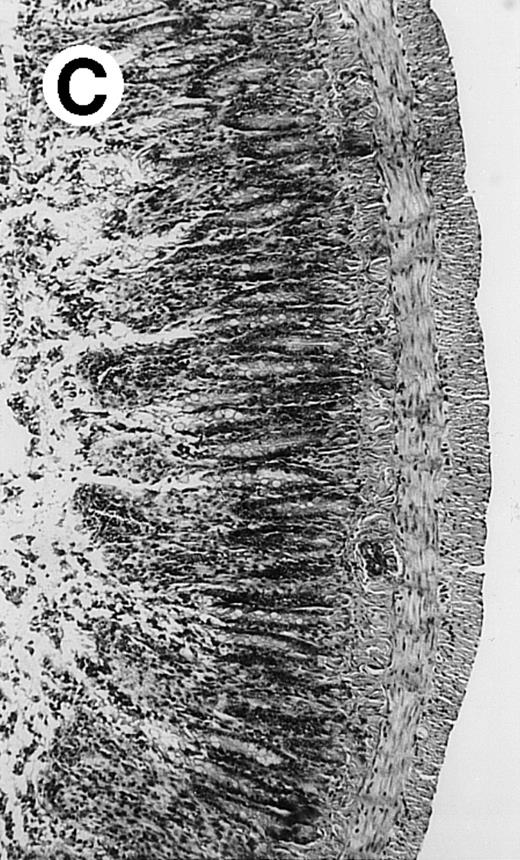

Pathologic findings in the small and large intestine were strikingly different depending on the treatment group. Figure 2A shows a representative pathologic sample from an animal assigned to the control group. Marked thinning of the bowel wall and extensive areas of epithelial cell sloughing was noted. Animals randomized to rhG-CSF treatment had minimal improvement in histologic findings with focal regions of preserved epithelium (Fig2B). Animals randomized to the rhIL-11 group showed substantial improvement with thickening of the epithelial layer and preservation of mucosal cell integrity (Fig 2C). Animals receiving both rhG-CSF and rhIL-11 had the most favorable histologic findings with normal mucosal thickness, minimal inflammatory changes, and preserved tissue architecture (Fig 2D). The composite analysis of the gastrointestinal pathology is provided in Table 1.

Histopathology of small intestinal mucosa cut in transection from an animal in each treatment group (study day 8). The upper panel (row 1) is a low power view (original magnification × 57); the lower panel (row 2) is a high power view (original magnification × 144). Note the diffuse thinning and necrosis of the mucosa with sloughing of intestinal epithelial cells in the control animal (A). There is progressive recovery of the thickness of the mucosa, reduction in inflammatory changes, and improved epithelial architecture with rhG-CSF (B), rhIL-11 (C), and combination therapy with rhG-CSF+IL-11 (D).

rhIL-11 has been shown to have marked effects on gastrointestinal epithelial surfaces. rhIL-11 blocks apoptosis of epithelial cells exposed to radiation and chemotherapy in mice.22 rhIL-11 is protective in a variety of mucositis models and in models of intestinal inflammation.4,23,24 rhIL-11 has been shown to prolong the G-0 phase of growth of intestinal epithelial cells. The precise mechanism of action is not known, but it has been observed that rhIL-11 decreased pRB (retinoblastoma protein) phosphorylation (an important signaling event in cell cycling) within intestinal epithelial cells.32 rhIL-11 has protective effects on gastrointestinal mucosa in transgenic rats, which possess HLA-B27 antigens.4These animals develop an inflammatory colitis that is similar in many respects to human inflammatory bowel disease. rhIL-11 treatment in these animals decreases intestinal inflammation and chronic diarrhea. Based on these preclinical findings, rhIL-11 is currently in clinical trials in both inflammatory bowel disease and chemotherapy-induced mucositis.33 The remarkable capacity of rhIL-11 to protect the gastrointestinal mucosal integrity after chemotherapy is apparent in the current series of experiments (Fig 2).

The beneficial effects of rhIL-11 in the neutropenic rat model may be mediated by its activity as a hematopoietic growth factor, an antiinflammatory cytokine, or its ability to maintain gastrointestinal epithelial integrity.25,33 The results of the current study would favor rhIL-11 protective effects on the intestinal epithelium as the principal mechanism protection in these animals. Maintenance of the gastrointestinal barrier function should diminish the frequency of gut translocation-derived bacterial infection after chemotherapy-induced myelosuppression and epithelial injury.25 The remarkable preservation of membrane integrity found on the gastrointestinal pathologic samples, the reduced circulating levels of endotoxin, and the reduced bacterial load in organ cultures support a dominant role for epithelial protective effects by rhIL-11 treatment in this animal model.